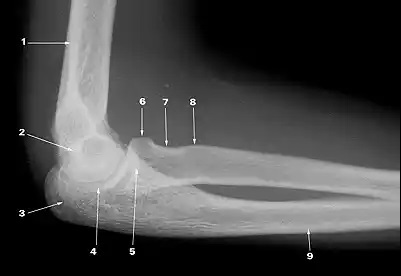

What does 1 indicate?

supracondylar ridge

What does 2 indicate?

trochlea

What does 6 indicate?

capitulum

What does 3 indicate?

olecranon process

What does 4 indicate?

trochlear notch

What does 5 indicate?

coronoid process of ulna

What does 8 indicate?

tuberosity of radius